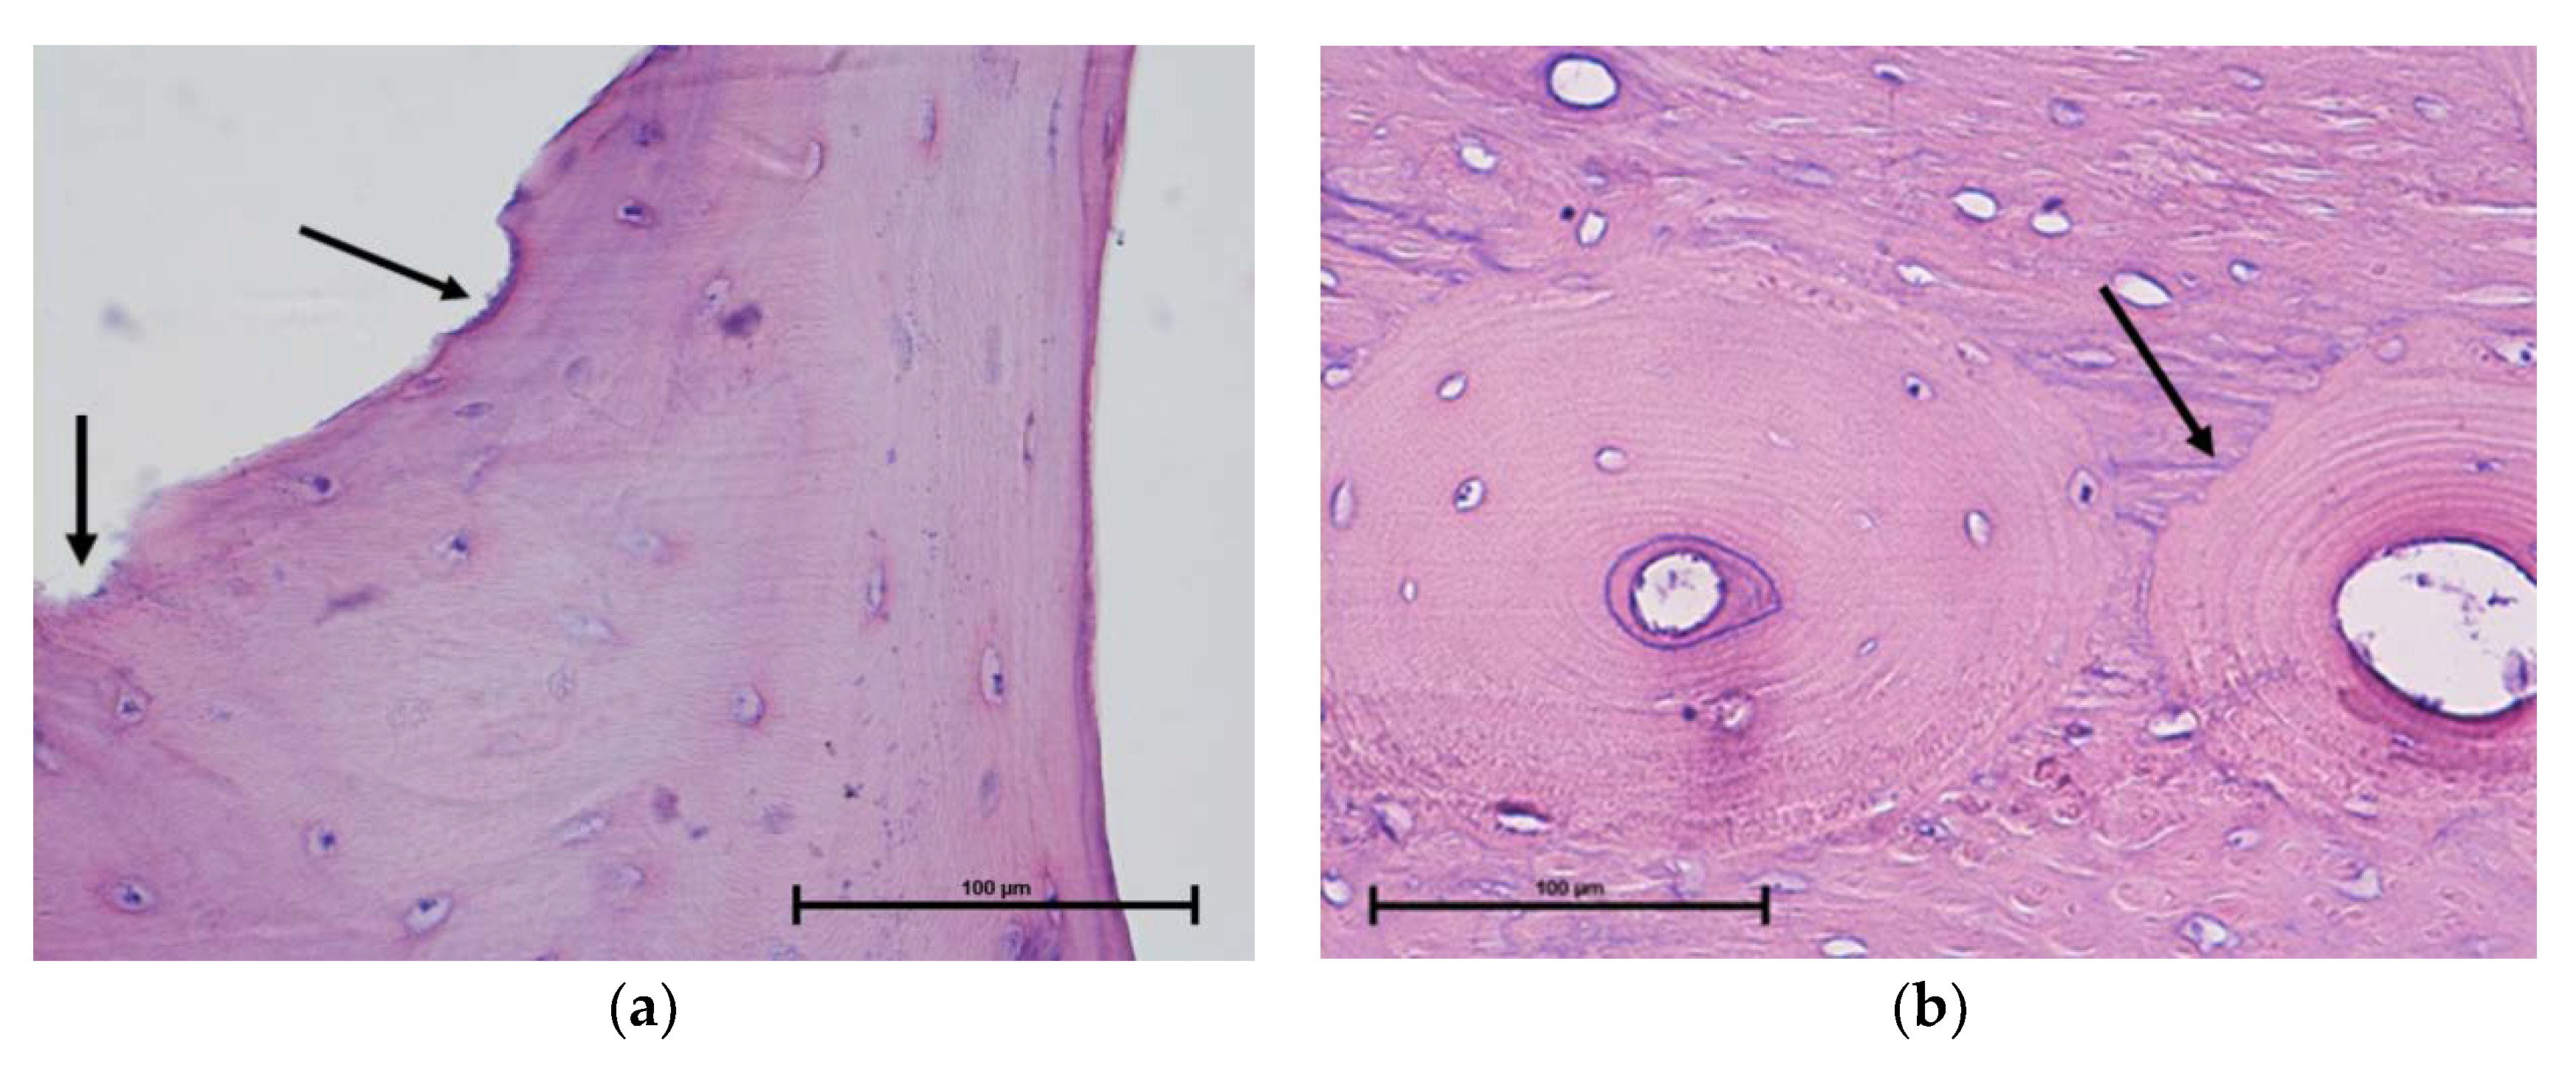

3.3.2. Histological Studies

- Kiełbowicz, Z.; Piątek, A.; Biezyński, J.; Skrzypczak, P.; Chmielewska, E.; Kafarski, P.; Kuryszko, J. Improvement of Large Animal Model for Studying Osteoporosis. Bull. Vet. Inst. Pulawy 2015, 59, 123–128. [Google Scholar] [CrossRef]

- Kiełbowicz, Z.; Piątek, A.; Bieżyński, J.; Skrzypczak, P.; Kuropka, P.; Kuryszko, J.; Nikodem, A.; Kafarski, P.; Pezowicz, C. The experimental osteoporosis in sheep – clinical approach. Pol. J. Vet. Sci. 2015, 18, 645–654. [Google Scholar] [CrossRef][Green Version]